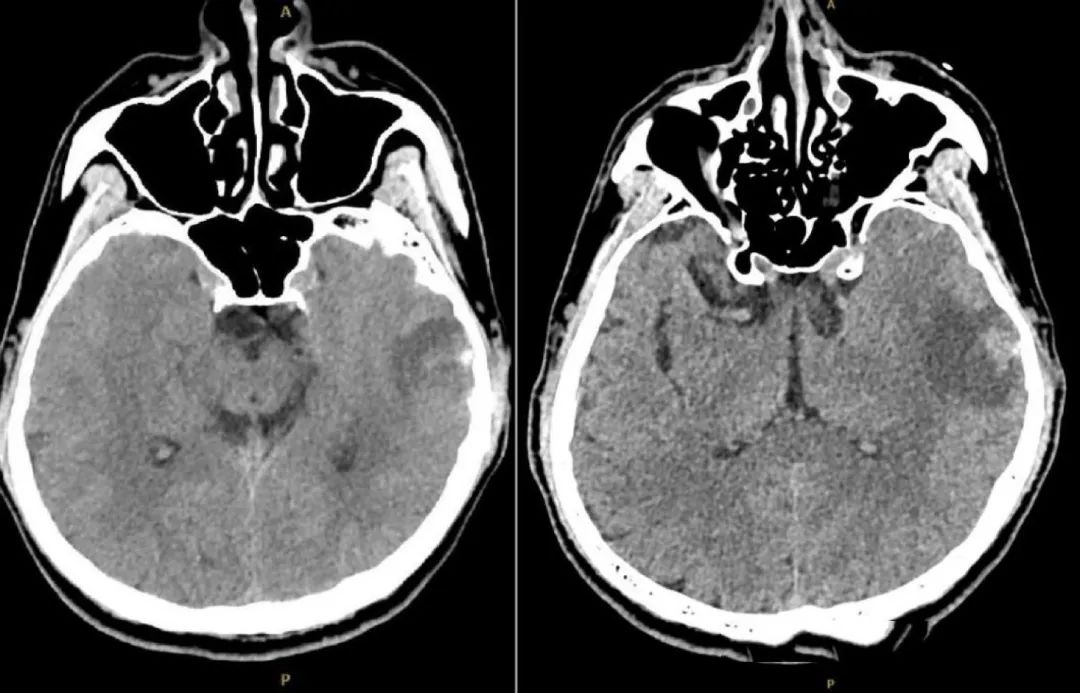

经检查,刘同学的大脑状态在短时间内急剧恶化,多处脑出血和肿胀、头颅CT血管影像中很多静脉血管消失。

图1. 头颅CT(发病后1周):左侧颞叶血肿可能。